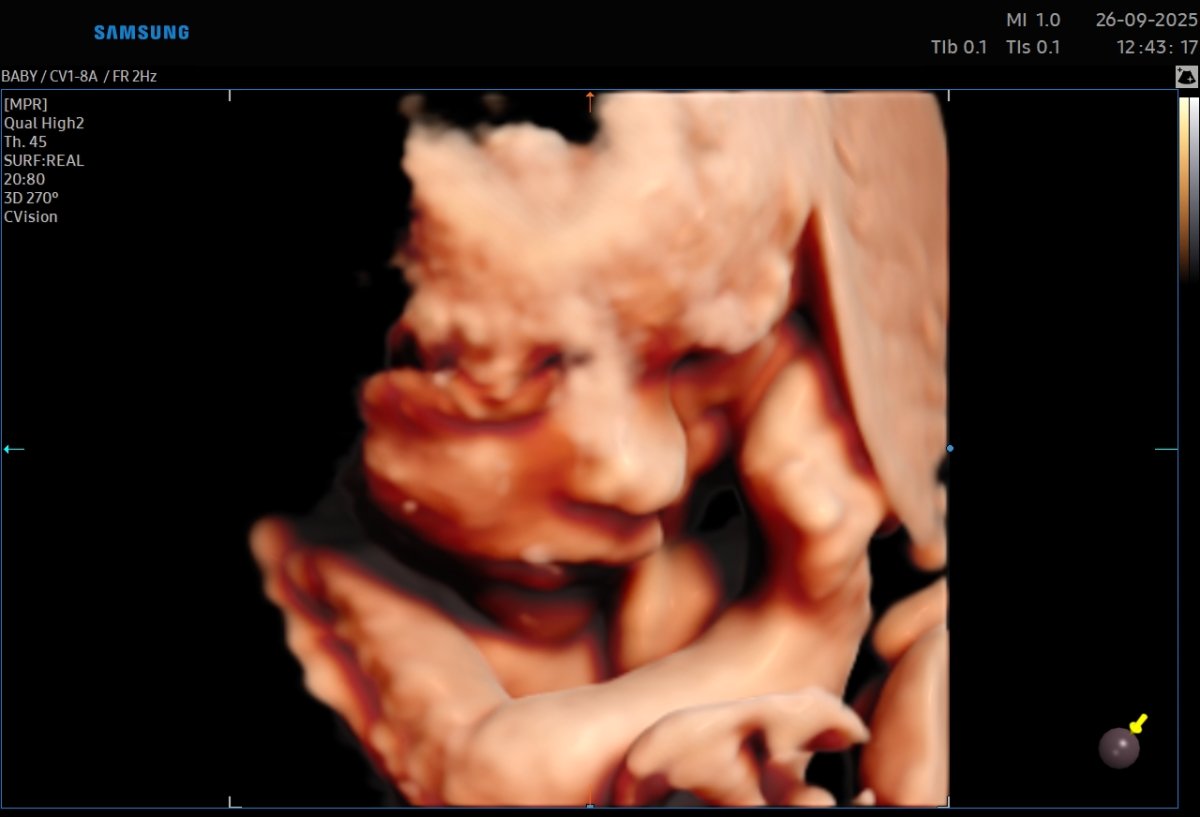

Gallerie de photos